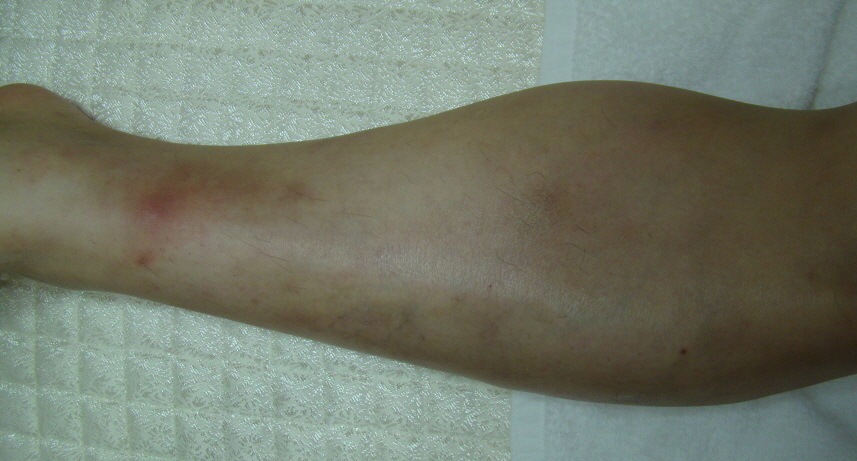

하지에 콩알만한 크기로 몽우리나 결절이 생기는 질환으로 결절홍반이 있습니다. 주로 하지 피부에 홍반성 압통성 결절, 쉽게 말해 색이 붉고 만지면 아픈 몽우리가 생기는 것이 대표적인 증상입니다.

이러한 결절은 주로 하지에 생기지만 안면부, 상지, 체간에도 생길 수 있습니다. 환부가 붉어지면서 통증이 있는 결절에는 열감이 동반되기도 합니다.

<결절홍반>